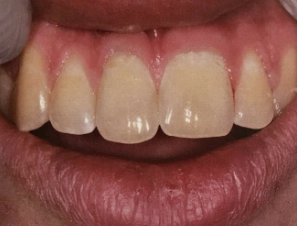

from use during tooth development; may also discolor skin, sclera, thyroid; RX for acne, cystic fibrosis, RA

tetracycline staining